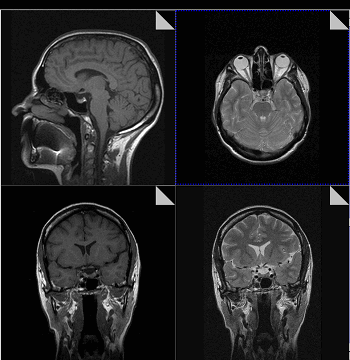

Магнитно-резонансная томография

В основе МРТ лежит явление магнитного резонанса, основанного на переизлучении радиоволн, взаимодействующих с атомами водорода, в избытке содержащимися в организме человека. Эти переизлученные электромагнитные волны улавливаются датчиком МР-томографа, усиливаются и в виде цифровых изображений появляются на экране монитора. Это безвредный и абсолютно безопасный для здоровья человека метод лучевой диагностики, так как в основе получения изображения отсутствует рентгеновское излучение, поэтому МРТ можно проходить неограниченное количество раз, с любым интервалом.

Существенное преимущество МР-томографии перед КТ заключается в том, что она не противопоказана беременным во II и III триместре и совершенно безопасна для детей. В МРТ исследуемая область сканируется в трех проекциях, что позволяет врачу-рентгенологу в полной мере оценить состояние тканей и органов исследуемой области, а высокая контрастность изображения и пространственное разрешение позволяют визуализировать серое и белое вещество головного мозга, оценивать состояние костного мозга и мягких тканей различной локализации. Кроме того, метод МРТ позволяет получать изображения сосудов головного мозга и сосудов шеи без введения контрастного препарата.

МРТ или магнитно-резонансная томография строит свою работу на принципе ядерного магнитного резонанса. Томограф работает с ядрами атомов водорода, которые есть в клетках тканей, имеющих воду составным элементом. Сначала аппарат МРТ создает сильное магнитное поле, а затем начинает на него воздействовать радиочастотным излучением. Протоны атомов водорода клеток пациента, находясь под таким воздействием, начинают колебаться и выстраиваются вдоль магнитного поля на очень короткий срок. Затем они возвращаются на исходные позиции, выбрасывая энергию. Именно ее улавливает компьютер МР-томографа и декодирует в трехмерные объемные, анатомически очень точные изображения.

Поскольку для хорошей визуализации магнитно-резонансному томографу нужно много клеток с атомами водорода, то ткани с большим содержанием воды лучше всего визуализируются на МРТ снимках. Поэтому МР-томография позвоночника очень хорошо показывает:

- спинной мозг;

- нервные волокна;

- сосудистое русло;

- мягкие ткани (мышцы, сухожилия, связки, межпозвоночные диски).